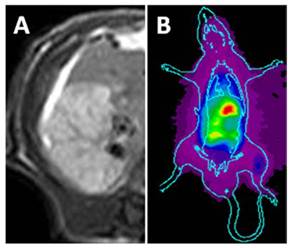

The necrotic liver lobe appeared homogeneously hypo- or iso-intense, but hyper-intense relative to the adjacent normal liver on T1 and T2 weighted MR images. On CE-T1 weighted image, reperfused necrotic liver lobe was hyper-enhanced by contrast agent (Fig. 2A).

Figure 2

In vivo MRI and planar gamma imaging of necrosis in RLI models. Liver lobe with reperfused infarction showed homogeneous hyper-enhancement on CE-T1 MR images (A). Planar gamma scintigraphy/radiography revealed a hotspot in the necrotic regions of the liver (B).

On planar scintigrams, the radioactivity gradually accumulated in the liver and intestines, reflecting quick hepatic uptake and biliary excretion of 123I-Hyp. From 24 h after injection, hot spot of high uptake could be easily found in the liver region (Fig. 2B), revealing high accumulation of radioactivity in the necrotic lobe. The hot spot image corresponds closely to the hyper-enhanced liver lobe on CE-T1 MR images.